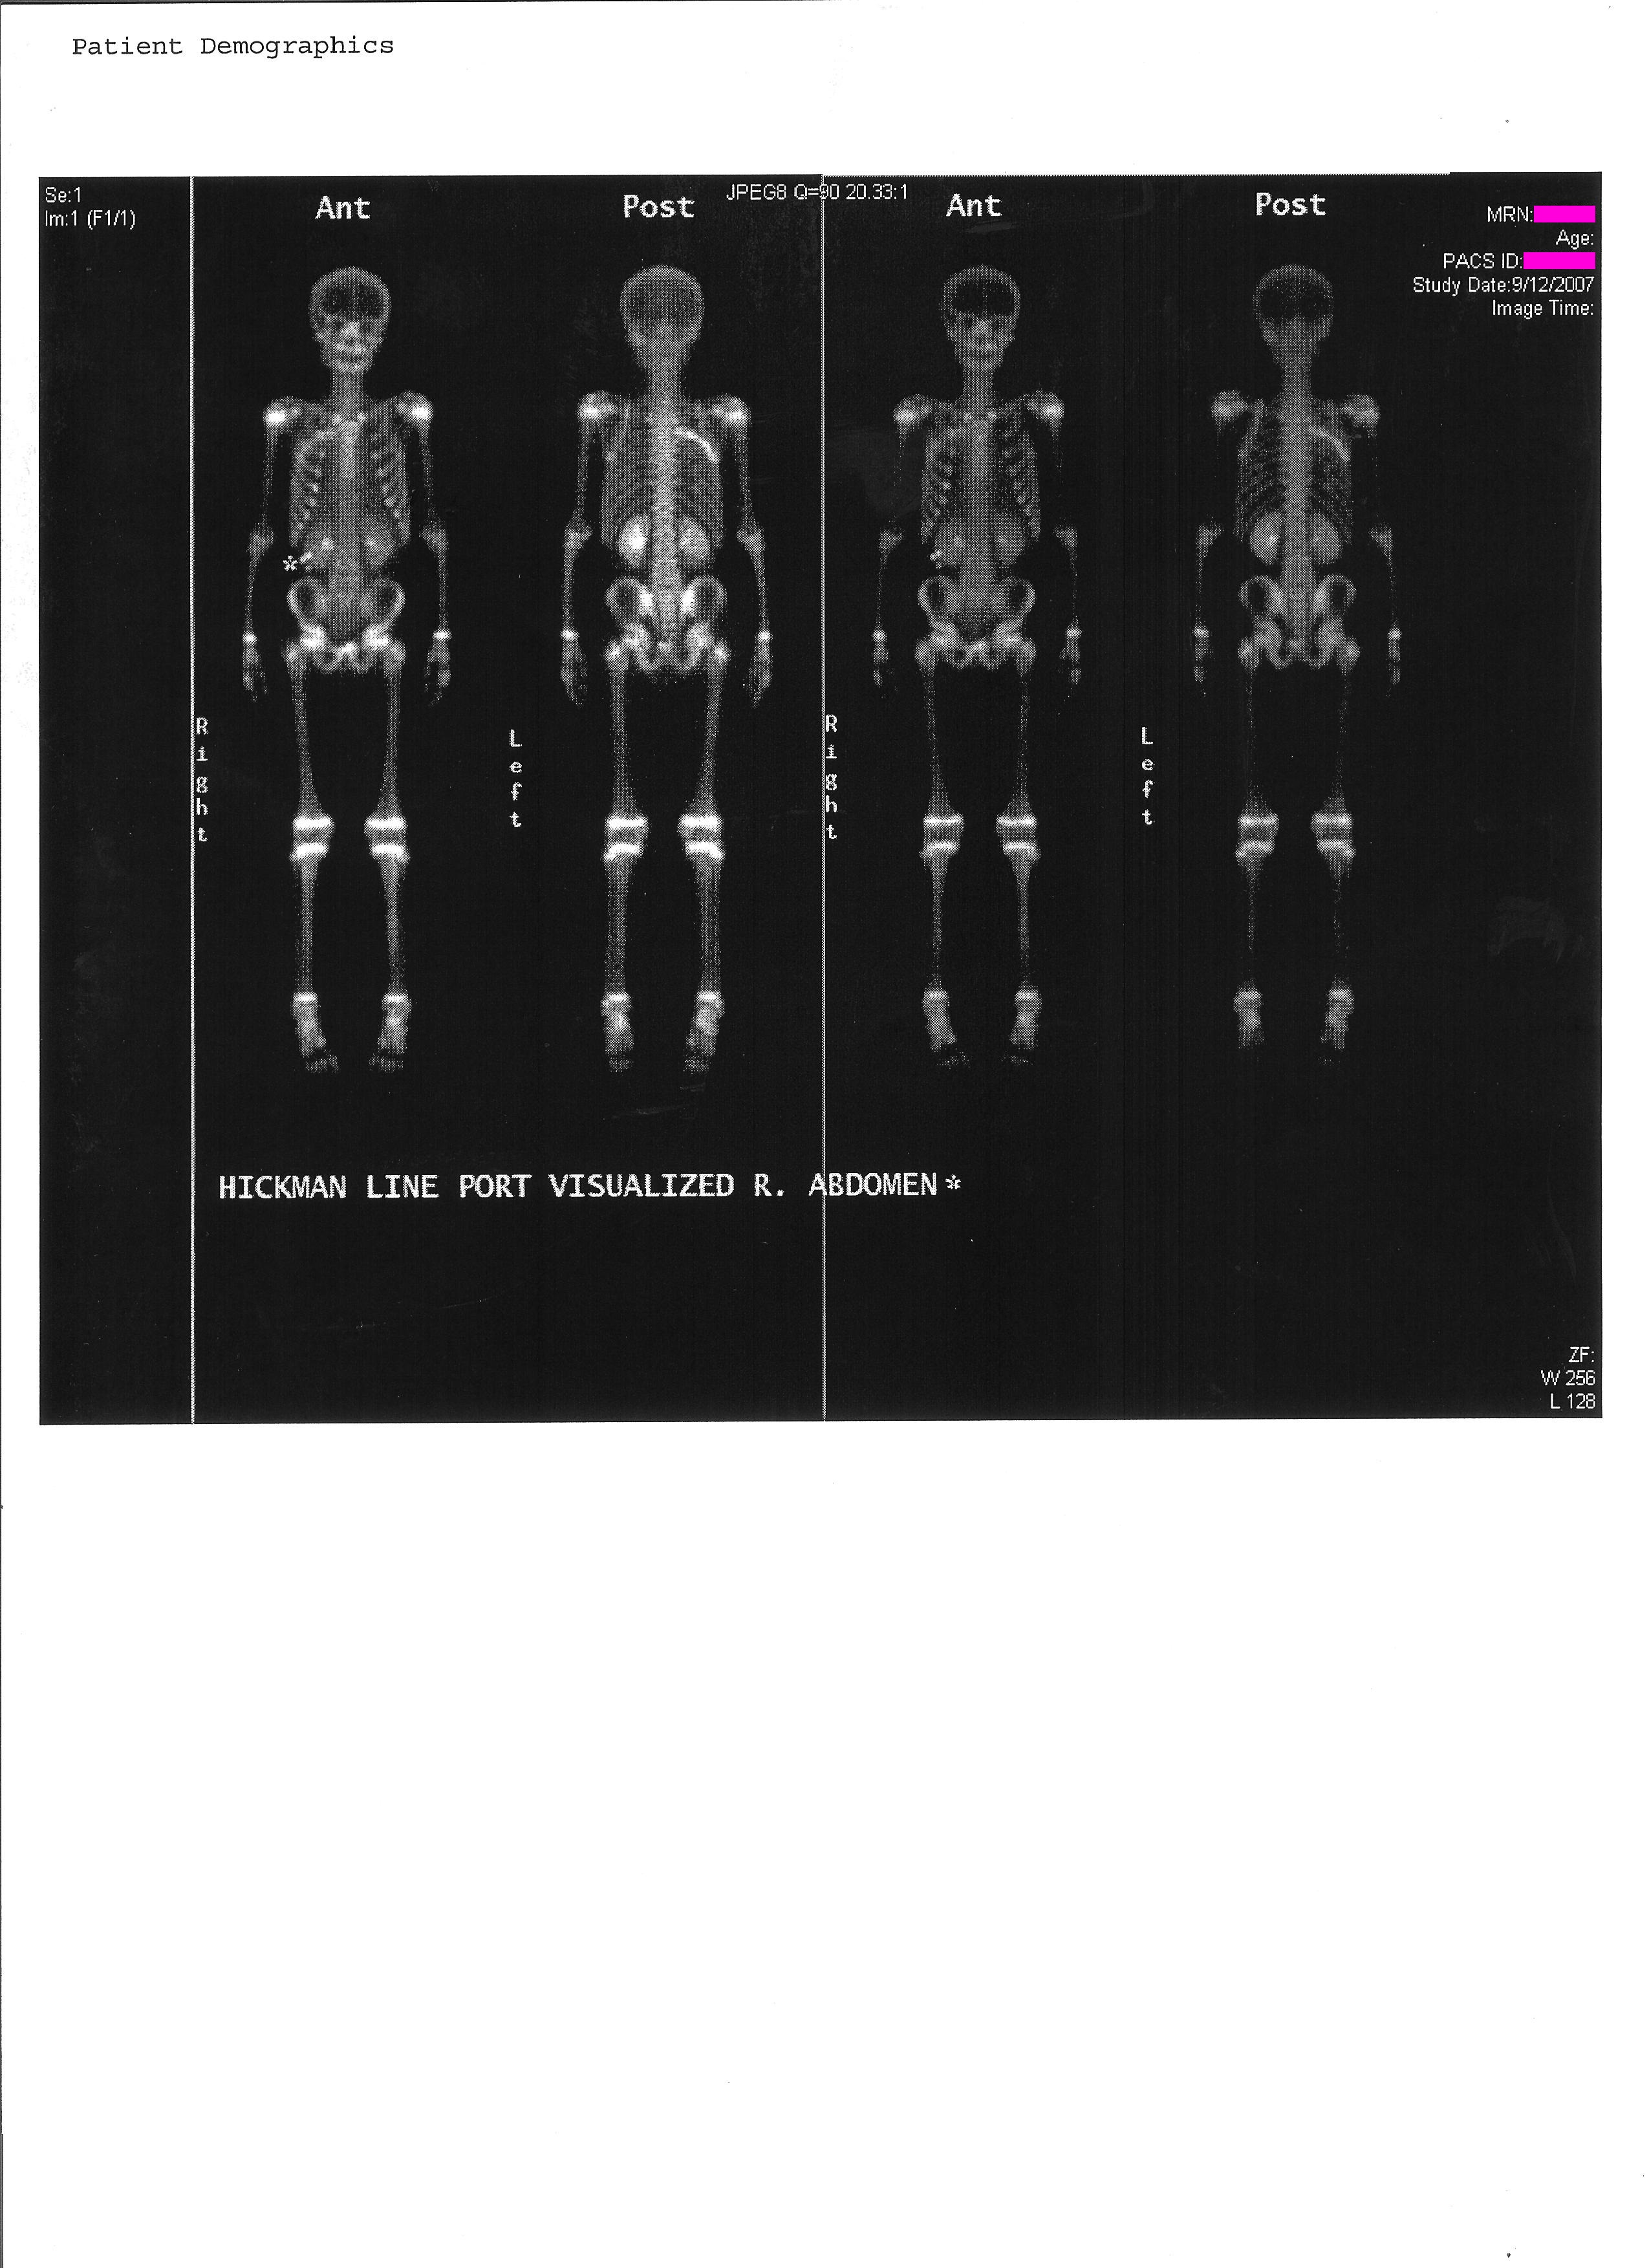

On June 25th 2007 I was diagnosed with Ewing's Sarcoma. This is a rare form of bone cancer typically only found in 10-20 year olds. This image is mirrored to reflect that the tumor was on the right side. You can click on any of the images for full images of the X-ray/Bone scan/CAT scan.

DeadSarcoma.png

For the next 4 months I was treated with # individual rounds of chemotherapy I was brought in for surgery to remove the tumor. This surgery removed 3 of my ribs, 4-6, from spine to armpit. These were replaced with a VEPTR, Vertical, Expandable, Prosthetic, Titanium, Rib. This prosthetic is clamped onto ribs 3 and 7 spanning the vertical gap. It also has titainum wires wrapped around and inserted into the remaining rib sections to emulate the ribs. Additionally a section of Gortex was added to strengthen the chest wall. Following this surgery I had another # chemotherapy treatments bringing the total up to 14 to total rounds. On March 1st 2008 I finished my last chemo treatment.